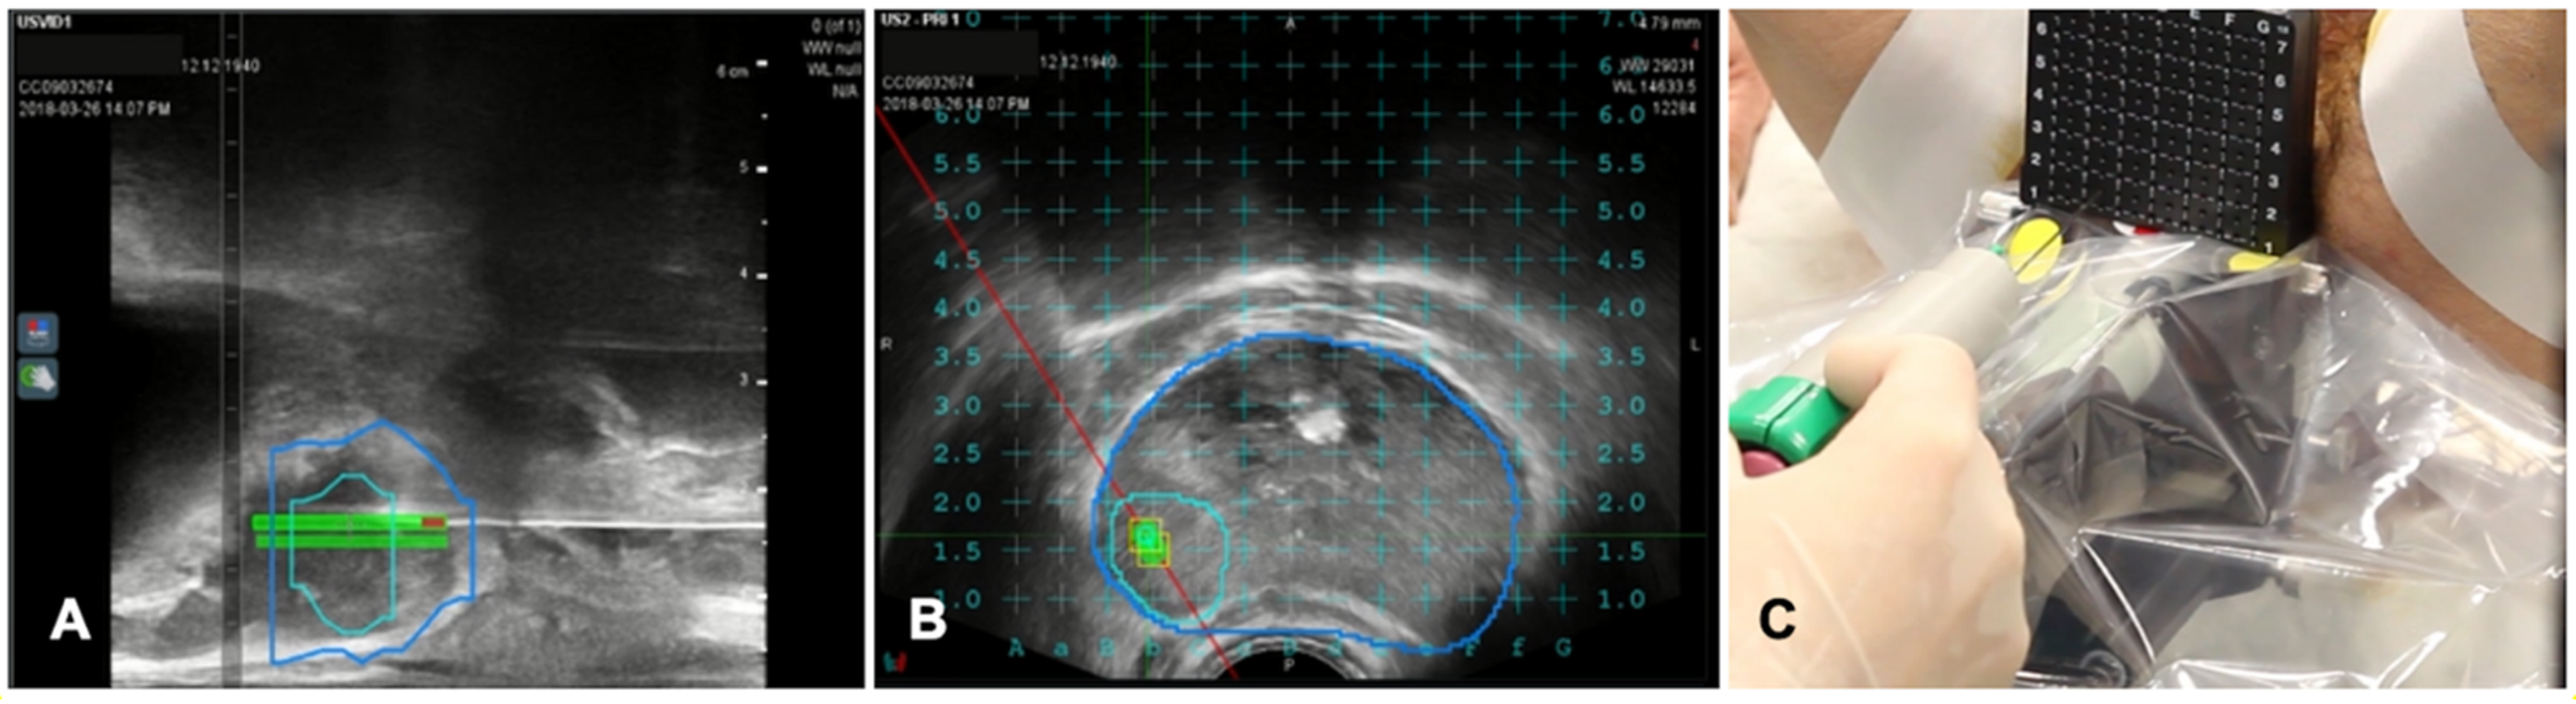

Some vendors provide locating device that can perform an automatic active tracking of the patient like the CIVCO omniTRAX (Civco Medical Instruments Co Inc. Kalona, IA, USA). This tool provides automatic image registration of fused images when using real-time US with previously acquired CT volume data sets and consists of a disposable locating device and an electromagnetic sensor. An example of a system for FI in a liver image guided ablation is shown in Figure 1.

Figure 6. Case of biopsies of a magnetic resonance imaging (MRI) visible prostate nodule. (A) Parasagittal long axis view of intraprocedural ultrasound fused with regions of interest from MRI. Target lesion has been segmented in MRI images and is encompassed by the green line in the prostate volume (blue line). (B) Axial view of the target lesion (green line) in prostate parenchyma (blue line) derived from MRI. A reference grid is superimposed to select the appropriate space for needle placement. (C) A transperineal biopsy needle is then placed in the selected hole in the reference grid and advanced into the target lesion.